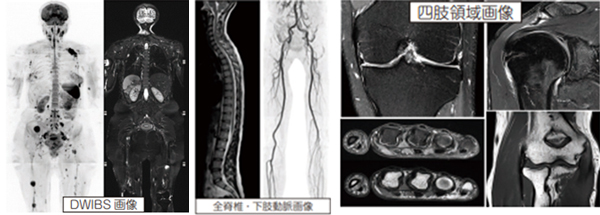

また、画像の厚みも従来の3~5mm 厚の画像から、更新後1~2mm の薄いスライスに変更しています。薄いスライスで高精細な画像は、当院の強みである整形外科領域において非常に有用な画像情報となっています。小さな椎間板ヘルニア・半月板損傷・腱板断裂や小さな関節評価(顎関節・指等)はもちろんのこと、全脊椎・上/下半身等の広範囲な部位まで詳細な画像が提供できます。脳外科領域の脳・神経・血管の評価や泌尿器科領域での前立腺癌評価においても、小さな病変の段階から、より高精度・高感度で描出できるため、早期発見・早期治療へ大きな手助けとなることが期待されます。さらに MRI 装置を利用した新しい全身がん検診技術DWIBS(ドゥイブス)と呼ばれる撮像が可能となるため、全身のがん検索についても安価で簡単に行うことができます。